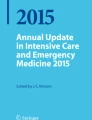

Cranial Bone Thickness and Cerebrospinal Fluid Layer

Cranial bone thickness varies between individuals. In NIRS the path length of the photon tends to be longer with a greater bone thickness. The volume of the cerebrospinal fluid layer is determined by the size of the space between the brain parenchyma and the cranial bone, as shown on the head CT scan in Fig. 5. A larger cerebrospinal fluid volume is associated with a smaller number of photons reaching the brain parenchyma and, therefore, an underestimation of rSO2 [92].

Impact of skull thickness and the cerebrospinal fluid layer on NIRS oxygenation monitoring measurements (arranged from the figure in [91])